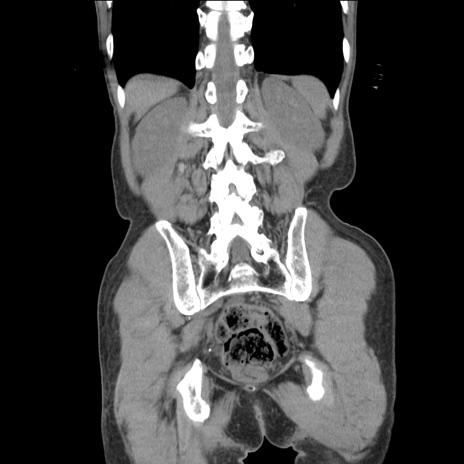

症例11(冠状断像)

【症例】 60歳代男性

【主訴】 下腹部痛

【現病歴】 本日夜中より下腹部痛の症状認め、受診。

【既往歴】 膀胱癌(膀胱全摘+尿管皮膚瘻術) 、胃癌術後

【身体所見】 BT 35.3℃、PR 58/min、BP 136/98mHg、腹部平坦、軟、腸蠕動音±、ストマ留置あり、左上腹部~正中部に圧痛あり、反跳痛なし。

【データ】WBC 5100、CRP0.01